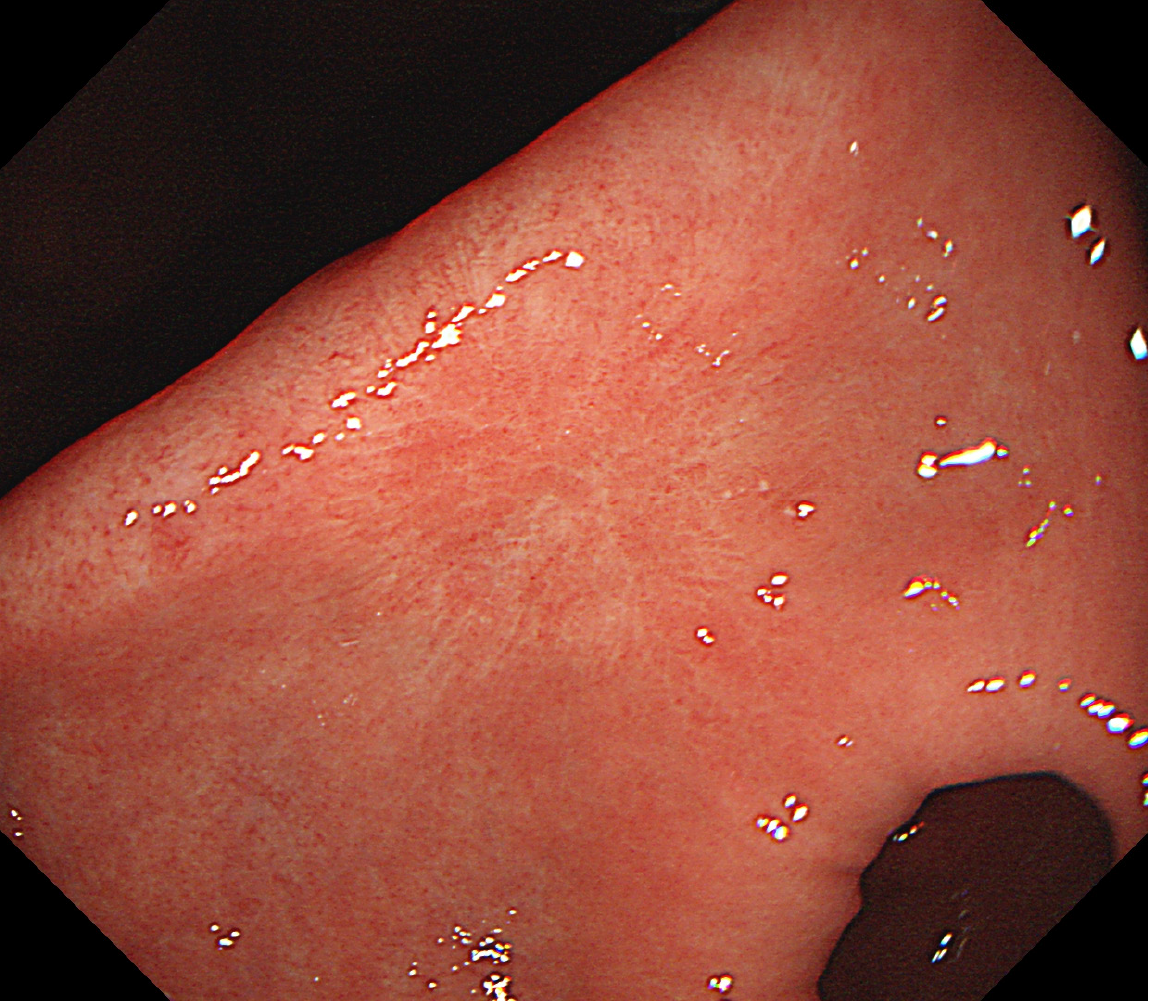

Figure 1 Endoscopic presentation of gastric antrum.

A: Multiple ulcers of the gastric antrum (white arrow) (2021-02-03); B: An ulcer on the small-curvature side of the antrum (2021-12-30).